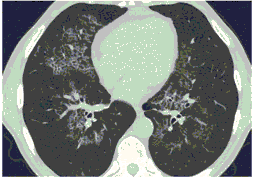

2. Наличие клинических проявлений, указанных в п. 1, в сочетании с характерными изменениями в легких по данным компьютерной томографии (КТ) (см. Приложение 1 настоящих рекомендаций) вне зависимости от результатов однократного лабораторного исследования на наличие РНК SARS-CoV-2 и эпидемиологического анамнеза.

- Изменения при КТ (рентгенографии), типичные для вирусного поражения (объем поражения минимальный или средний; КТ 1-2)

- Изменения в легких при КТ (рентгенографии), типичные для вирусного поражения (объем поражения значительный или субтотальный; КТ 3-4)

- Изменения в легких при КТ (рентгенографии), типичные для вирусного поражения критической степени (объем поражения значительный или субтотальный; КТ 4) или картина ОРДС.

КТ имеет высокую чувствительность в выявлении изменений в легких, характерных для COVID-19. Применение КТ целесообразно для первичной оценки состояния ОГК у пациентов с тяжелыми прогрессирующими формами заболевания, а также для дифференциальной диагностики выявленных изменений и оценки динамики процесса. КТ позволяет выявить характерные изменения в легких у пациентов с COVID-19 еще до появления положительных лабораторных тестов на инфекцию с помощью МАНК. В то же время, КТ выявляет изменения легких у значительного числа пациентов с бессимптомной и легкой формами заболевания, которым не требуется госпитализация. Результаты КТ в этих случаях не влияют на тактику лечения и прогноз заболевания при наличии лабораторного подтверждения COVID-19. Поэтому массовое применение КТ для скрининга асимптомных и легких форм болезни не рекомендуется.

15. Рекомендации по формированию описаний и оценке изменений в легких и ОГК при имеющейся/подозреваемой пневмонии COVID-19 представлены в Приложении 1.